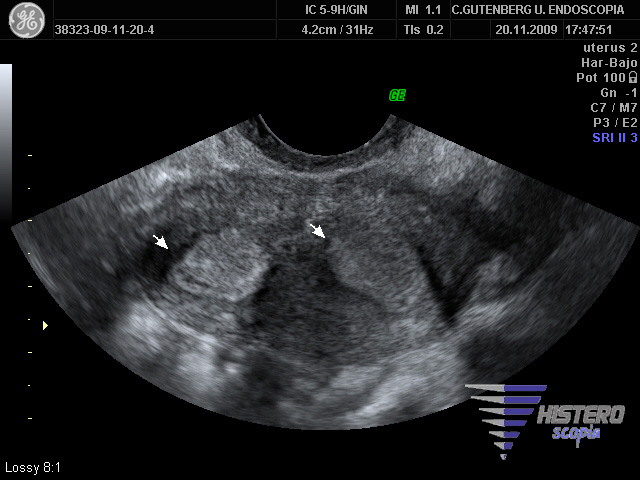

La prueba inicial para el diagnóstico es la ecografía transvaginal que nos permite un diagnóstico muy acertado en la mayoría de los casos. Para esta valoración ecográfica es importante conocer la metodología de valoración ecográfica de Fedele, en la que tras trazar una linea imaginaria que une los dos ostium, se mide la distancia entre esta linea y el borde superior uterino, si es mayor de 5mm es un septo y el utero puede abordarse por via histeroscópica.